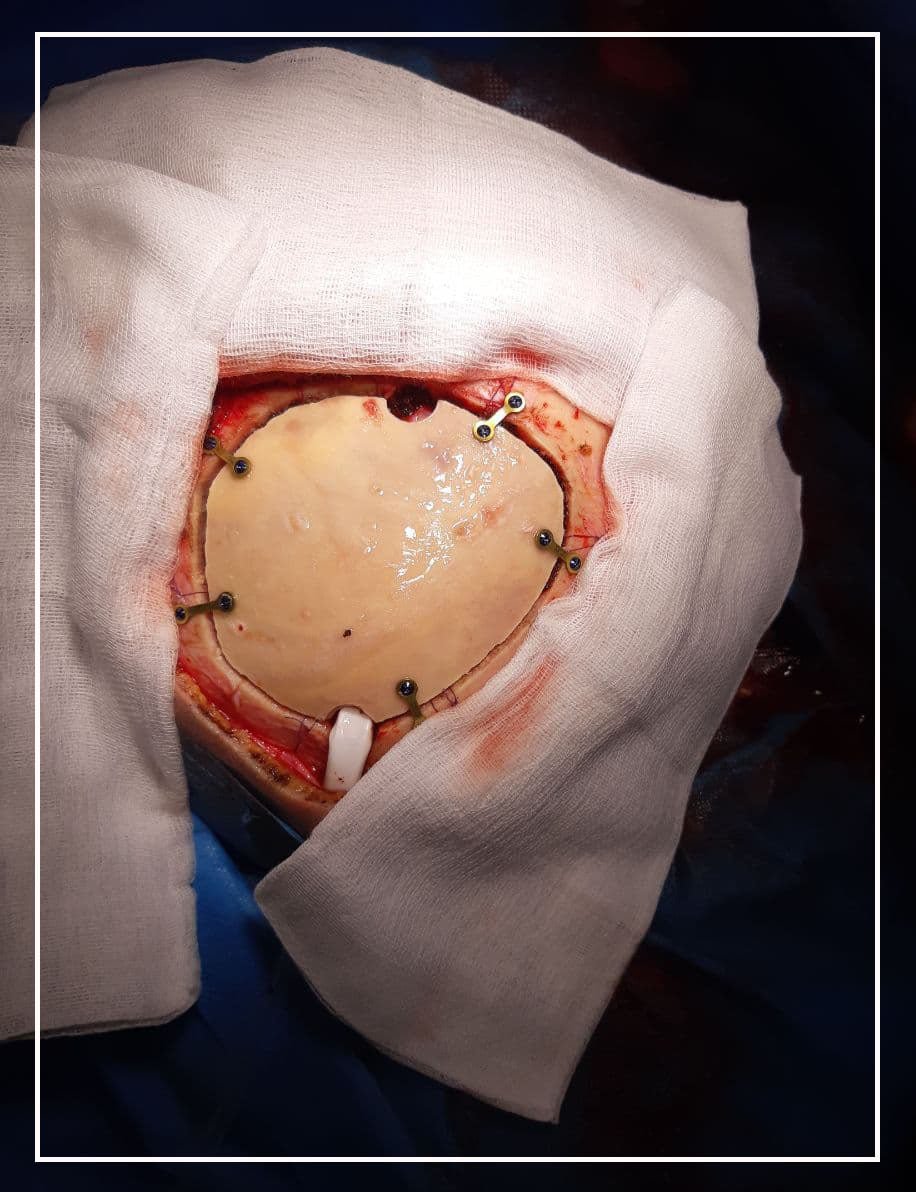

Цар тахлын энэ үед ГССҮТ-ийн гавал, тархины гэмтлийн тасгийн эмч нар улаан бүсэд ковидын халдвараар оношлогдсон 51 настай үйлчлүүлэгчийн тархины эдийн доторх цусан хураа авах төрөлжсөн мэргэжлийн мэс заслыг цаг алдалгүй амжилттай хийсэн байна.

Хүнд өвчтэй иргэнд мэс заслын тусламж үйлчилгээг тархины мэс заслын тасгийн их эмч, мэдрэлийн мэс засалч Э.Энхтүвшин, Ц.Эрдэнэ болон Ковидын тасагт ажиллаж байгаа 7 дугаар багийн хамт олон их эмч А.Амгаасэд, мэдээгүйжүүлгийн эмч Н.Оюунчимэг, сувилагч Адъяасүрэн, Мөнхтулга нар хамтран үзүүлжээ.